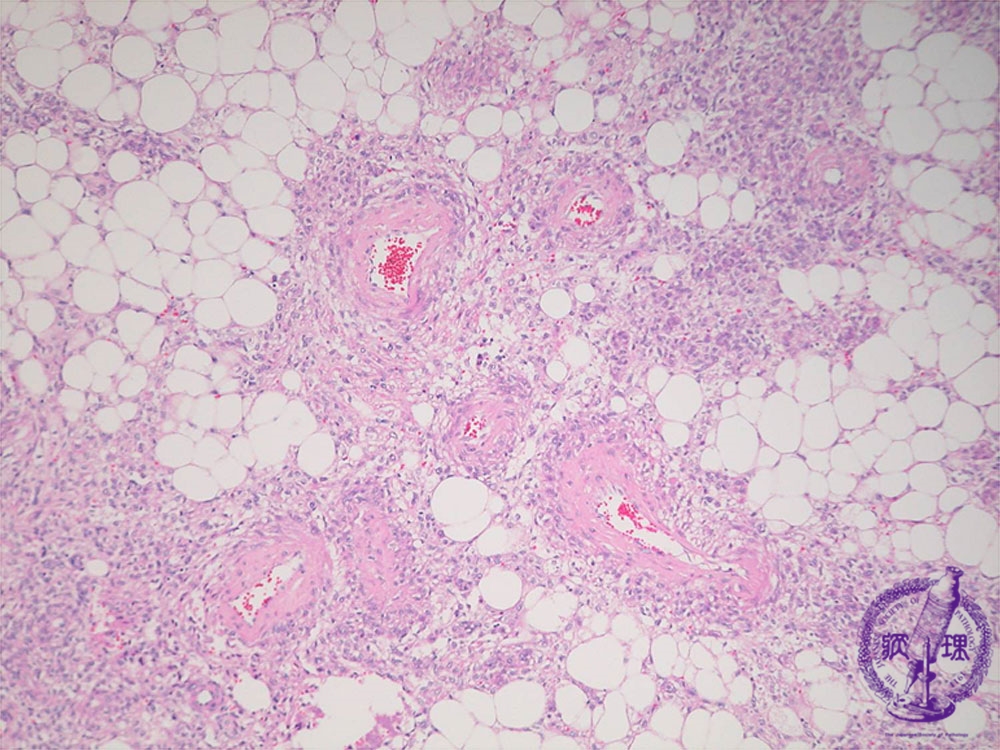

腎血管平滑筋脂肪腫(結節性硬化症)ミクロ像(HE中拡大)

ミクロ像(HE中拡大):腫瘍内では脂肪細胞、壁の肥厚を伴う血管、平滑筋細胞が認められる。